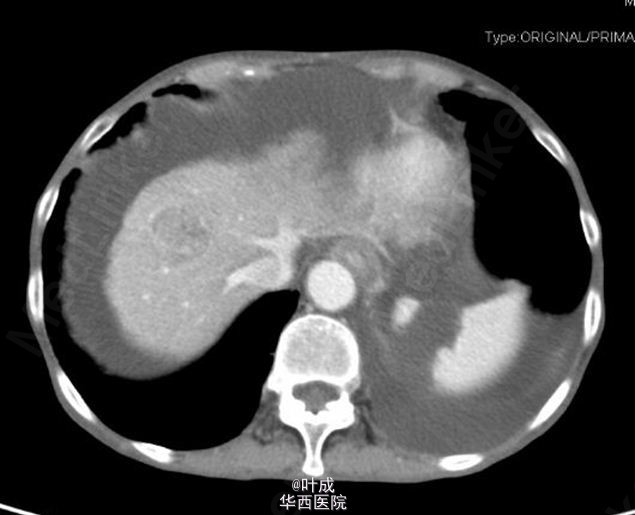

查体:T:37.2℃,P:98次/分,R:18次/分,BP:155/84mmHg,心肺查体无特殊,腹部膨隆,全腹软,上腹部轻压痛,无反跳痛,腹部未触及包块,肝肋下1-2cm,剑下5cm,质地较硬,脾脏肋下未触及,双下肢轻度水肿。 辅助检查:血常规:Hb 96 g/L,WBC 3.86 10^9/L,N 75.3 %;肝肾功:TB 18.0 umol/L,DB 10.7 umol/L,ALT 33 IU/L,AST 109 IU/L,ALB 25.6 g/L,ALP 142 IU/L,GGT 175 IU/L,肾功未见异常;AFP 214.50 ng/ml,CEA 4.23 ng/ml,CA19-9 89.39 U/ml,CA-125 478.40 U/ml;输血前检查:乙肝表面抗体、乙肝e抗体、乙肝核心抗体阳性,余阴性,高精度HBV病毒载量 阳性,<20 IU/mL;凝血常规、大小便常规未见异常;腹水常规示黄色微混,有核细胞 20 10^6/L,总蛋白 12.6 g/L。腹部增强CT:肝硬化,腹水,食管-胃底粘膜下、胃周静脉曲张,脾大;右半结肠肿胀,肝门区、肠系膜根部及腹主动脉周围淋巴结增多,部分增大,自发性腹膜炎?与旧片比较腹水明显增多,淋巴结明显增多。肝右前叶上段片团影,肝右前叶上段见一大小约2.8×2.8cm的稍低密度影,其内见稍高密度影,边界模糊,增强扫描呈不均匀强化(图1-3)。